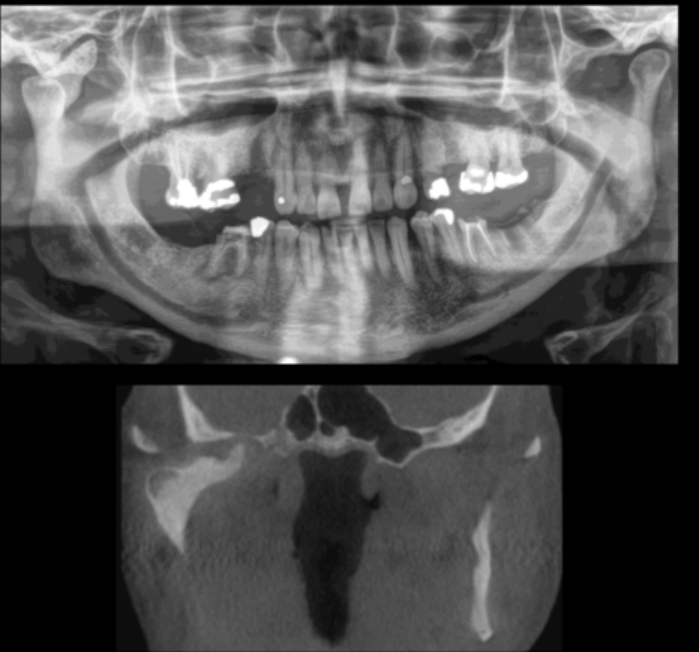

what does this show

beam hardening

what is this showing for the CBCT

volumetric rendering

bilateral view of TMJ